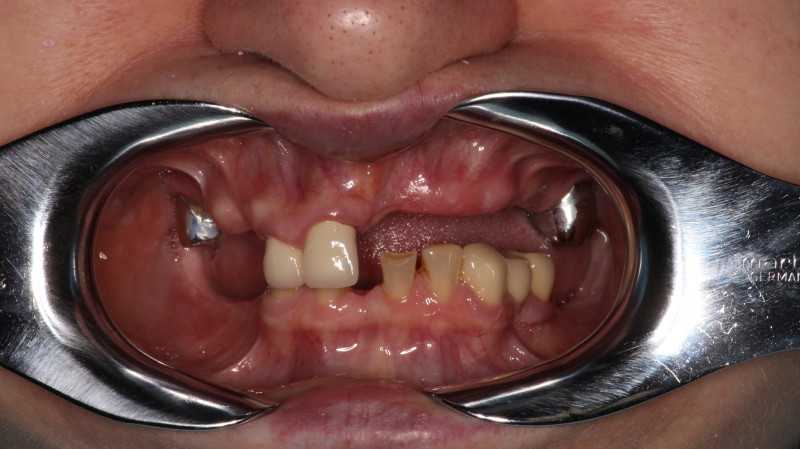

Имплантация верхнего зубного ряда по протоколу немедленной нагрузки